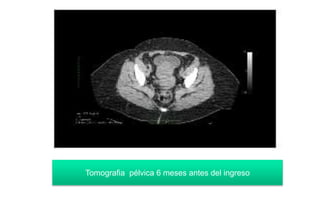

Tomografia pélvica 6 meses antes del ingreso

Tomografia pélvica 6meses antes del ingreso